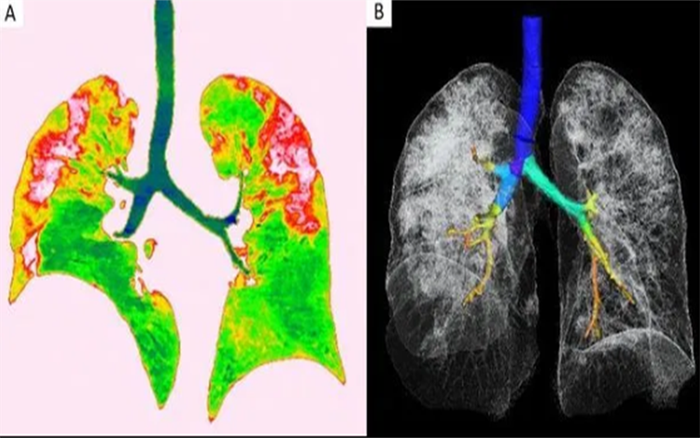

Ảnh chụp phổi của bệnh nhân nữ 54 tuổi.

Ảnh chụp cắt lớp lá phổi của một nữ bệnh nhân 54 tuổi bị nhiễm COVID-19 sau khi đến Vũ Hán cũng cho thấy hiện tượng tổn thương lan rộng như trên. Người phụ nữ này được chẩn đoán viêm phổi nặng do virus corona sau khi có dấu hiệu sốt, ho, mệt mỏi và tức nghẹn ở ngực trong khoảng một tuần. Bác sĩ đã cho bà thở oxy và dùng kháng sinh để đẩy lùi triệu chứng.

Tổn thương ở phổi của một người phụ nữ 45 tuổi ở tỉnh Tứ Xuyên, Trung Quốc dương tính với COVID-19.